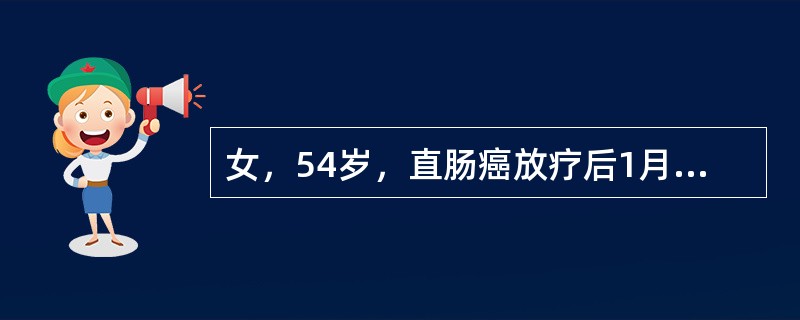

女,54岁,直肠癌放疗后1月,阵发性腹痛腹胀,呕吐应,CT表现如图,应诊断为()

女,54岁,直肠癌放疗后一月,阵发性腹痛腹胀,呕吐应,CT表现如图,应诊断为()<img border="0" style="width: 155px; heigh

[单选题]女,54岁,直肠癌放疗后一月,阵发性腹痛腹胀,呕吐应,CT表现如图,应诊断为()A.小肠淋巴瘤B.小肠结核C.小肠Crohn病D.放射性小肠炎E.肠易

女,54岁,直肠癌放疗后1月,阵发性腹痛腹胀,呕吐应,CT表现如图,应诊断为()

[单选题]女,54岁,直肠癌放疗后1月,阵发性腹痛腹胀,呕吐应,CT表现如图,应诊断为()A .小肠淋巴瘤B .小肠结核C .小肠Crohn病D .放射性小肠炎E .肠易激综合征

女,54岁,直肠癌放疗后1月,阵发性腹痛腹胀,呕吐,CT表现如图,应诊断为

[单选题]女,54岁,直肠癌放疗后1月,阵发性腹痛腹胀,呕吐,CT表现如图,应诊断为A . 小肠淋巴瘤B . 小肠结核C . 小肠Crohn病D . 放射性小肠炎E . 肠易激综合征

女,54岁,直肠癌放疗后1月,阵发性腹痛腹胀,呕吐,CT表现如图,最可能的诊断为

[单选题]女,54岁,直肠癌放疗后1月,阵发性腹痛腹胀,呕吐,CT表现如图,最可能的诊断为()A .小肠淋巴瘤B .小肠结核C .小肠Crohn病D .放射性小肠炎E .肠易激综合征